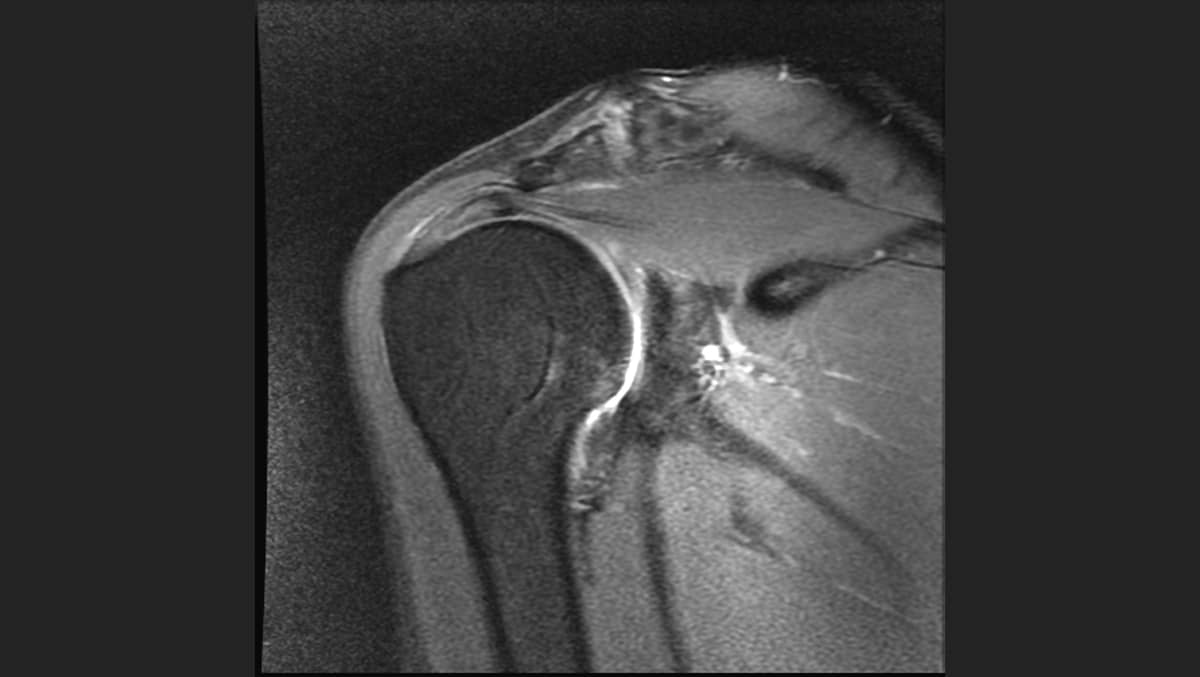

Once diagnosed, usually after a fall or an overuse injury (36 holes of golf rather than 18, a hard tennis match, or a Pickleball tournament) the workup with X-rays and MRIs often show both the acute and chronic damage. Then the decisions about care begin.

Dr. Stone: Again, it depends on a wide range of factors. These include the patient's physical presentation; how much dysfunction they have; what the X-rays look like in terms of arthritis; what the MRI looks like in terms of muscle-wasting or atrophy; and how much inflammation exists in the tendon.